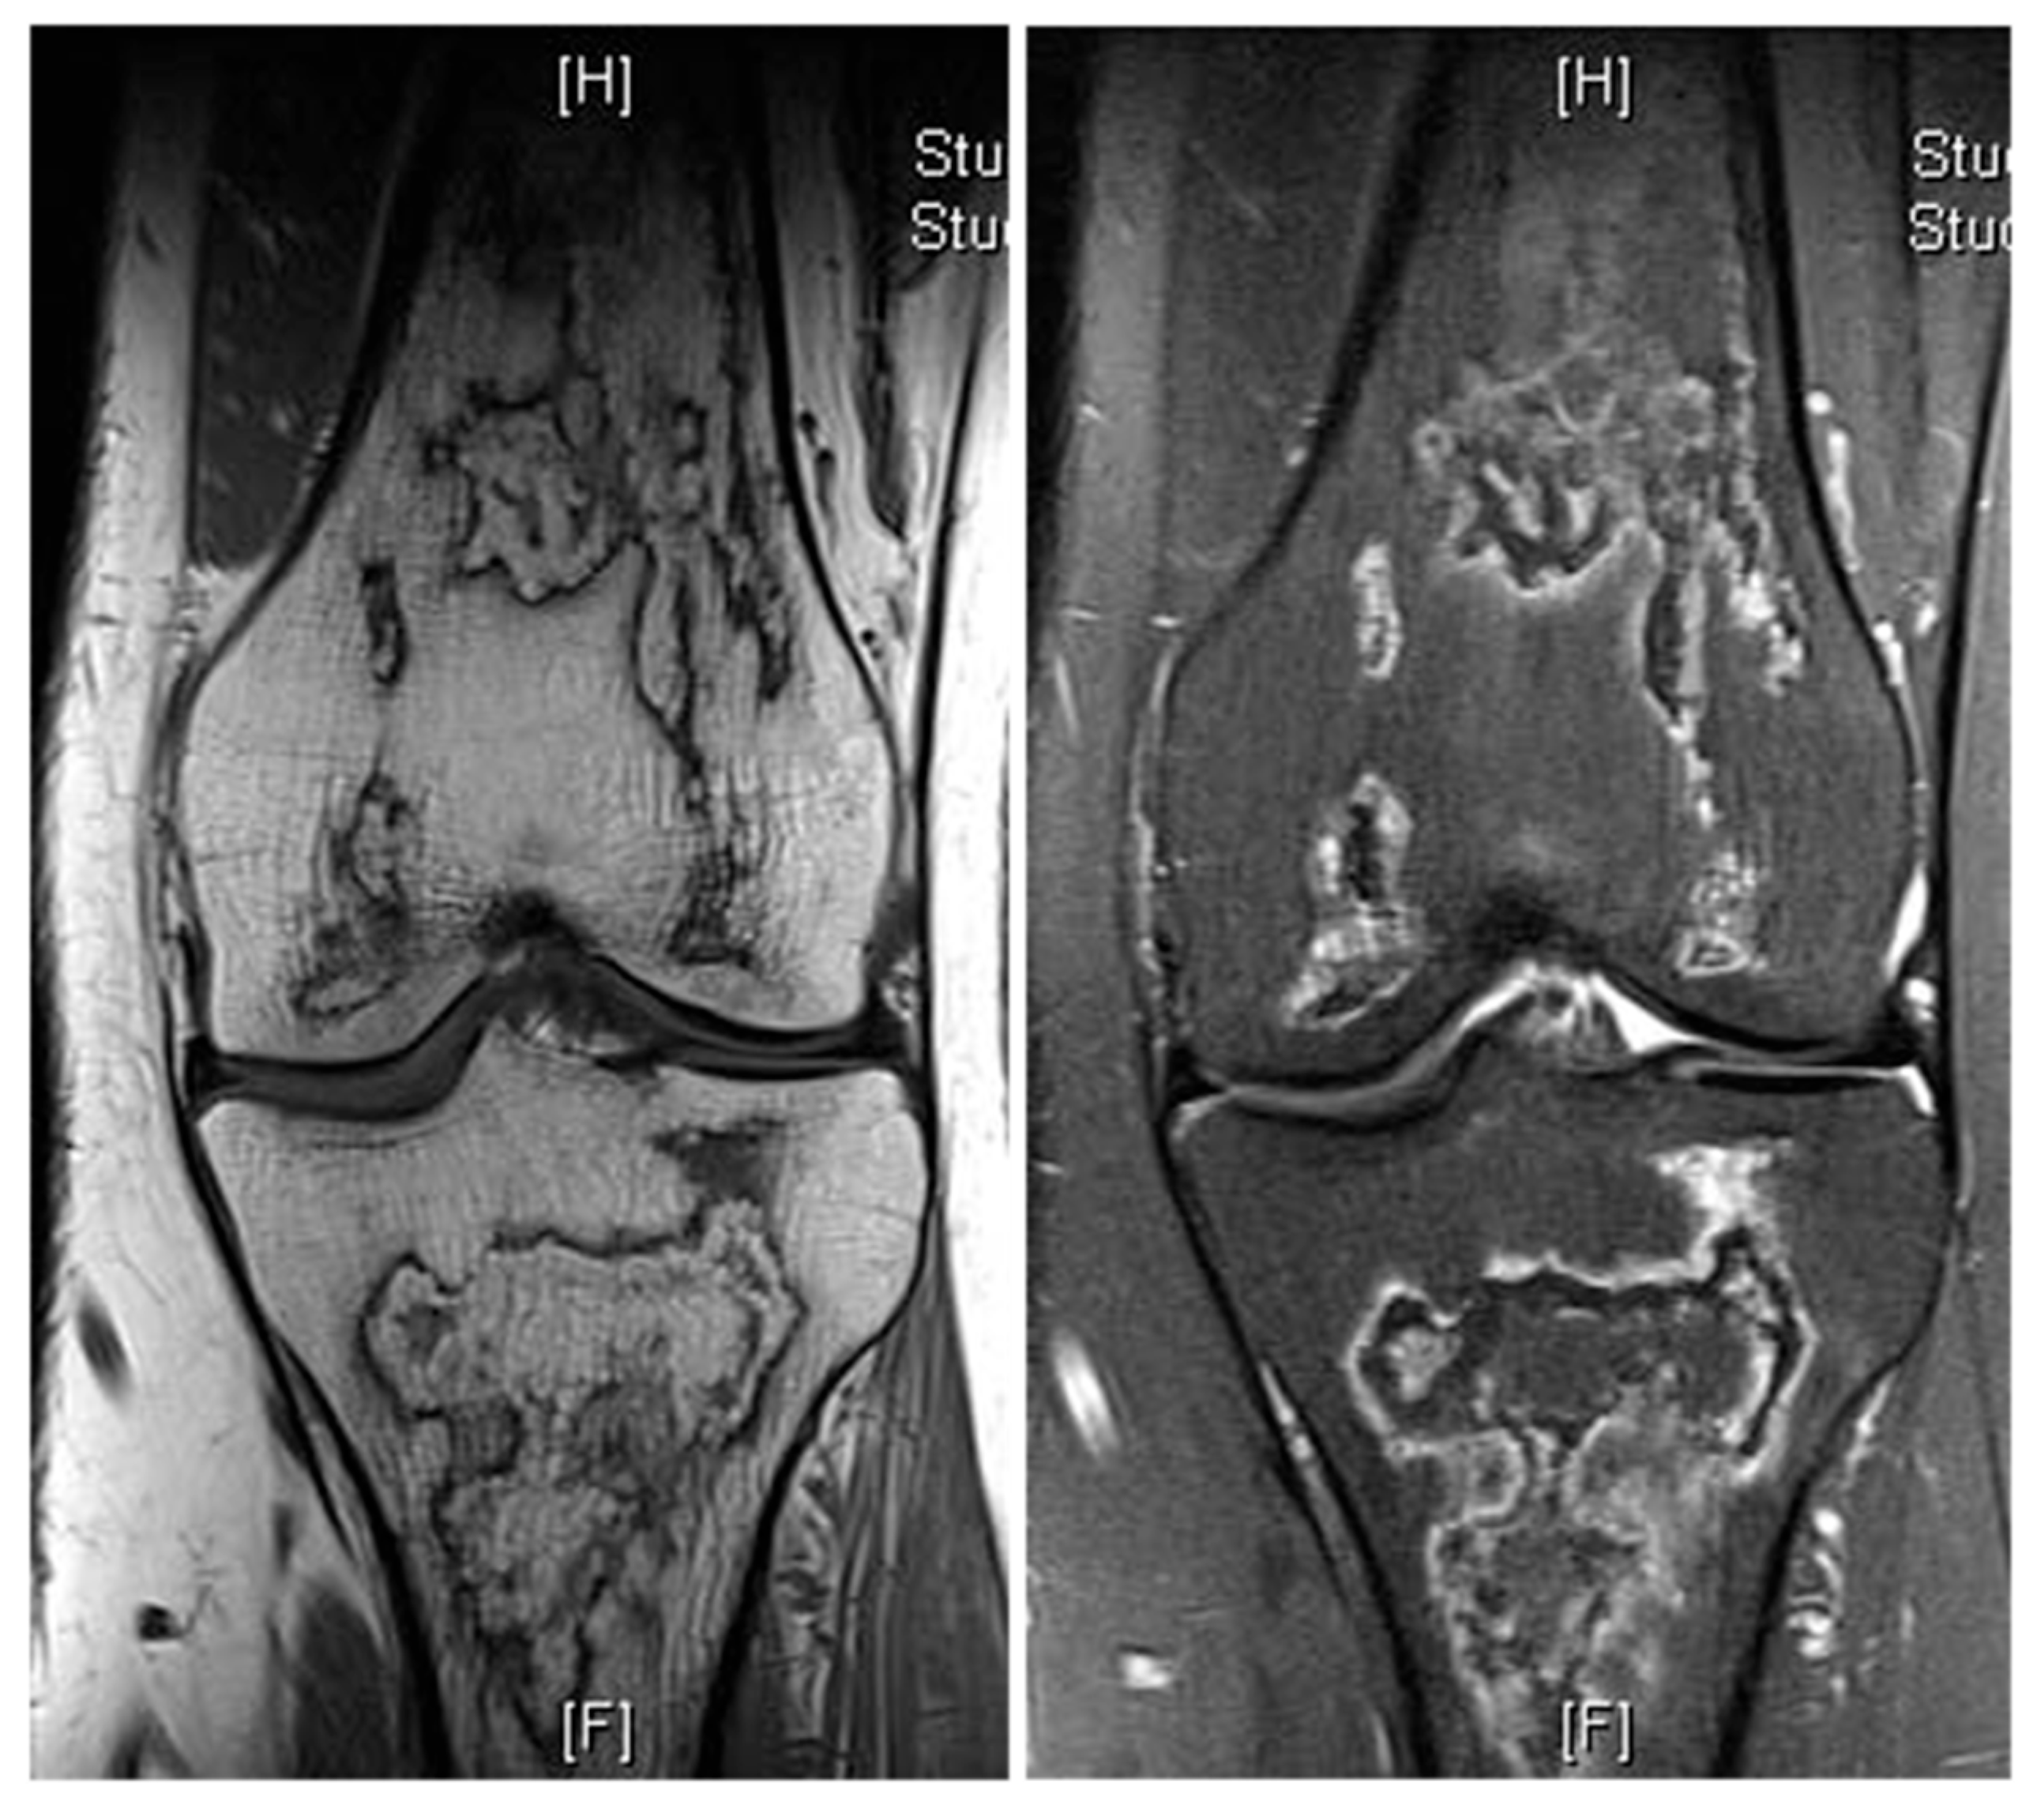

Figure 9.

Bone infarct knee. Coronal T1W and STIR knee MRI demonstrating serpiginous, peripheral low signal intensity with central fat intensity signal (high T1 and low STIR).